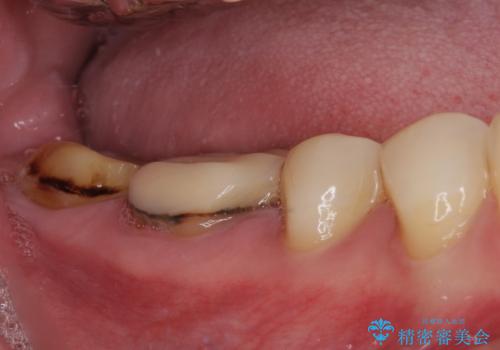

- 以前、職場近くで夜遅くまで治療していた医院で装着した奥歯のクラウンが、壊れたり汚れたりしていることを気にして来院された患者様です。

以前は安価であったことからハイブリッドクラウンを選択されたそうですが、すぐに具合が悪くなってしまったので、今回はオールセラミッククラウンにて補綴治療を行うこととしました。